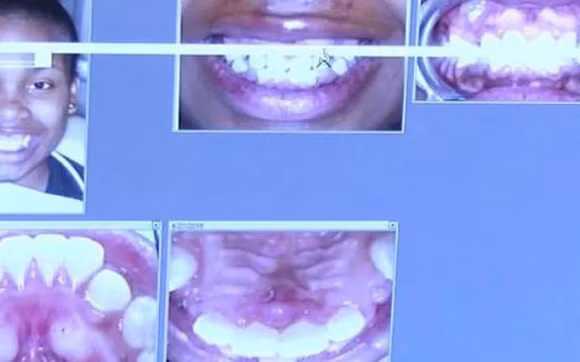

Kennedy Odom, 16 tuổi đã bị ốm và sốt cao thậm chí không thể đi học sau nhiều tháng niềng răng. Không những thế, miệng cô đau đớn và đầy mụn nước, không thể ăn vì đau dữ dội khi nhai nuốt. Khi đi khám, các bác sĩ cho rằng cô bé bị viêm họng và kê thuốc kháng sinh, giảm đau. Những triệu chứng của Kennedy không hề thuyên giảm mà còn nặng hơn. Rất may là sau đó một thành viên trong gia đình nhận thấy những triệu chứng như môi sưng tấy đỏ, nổi mụn nước… chỉ xuất hiện xung quanh vùng miệng cô bé nên đã yêu cầu các bác sĩ kiểm tra.

niềng răng, tai nạn niềng răng, tai nạn niềng răng đáng sợ trên thế giới

Sau khi làm xét nghiệm, kết quả cho thấy cô bé bị dị ứng niken toàn thân và thủ phạm khiến cô bé phải chịu đau bấy lâu nay chính là niken trong niềng răng. Chiếc niềng răng được tháo bỏ và các triệu chứng trên của Kennedy đã thuyên giảm ngay lập tức.